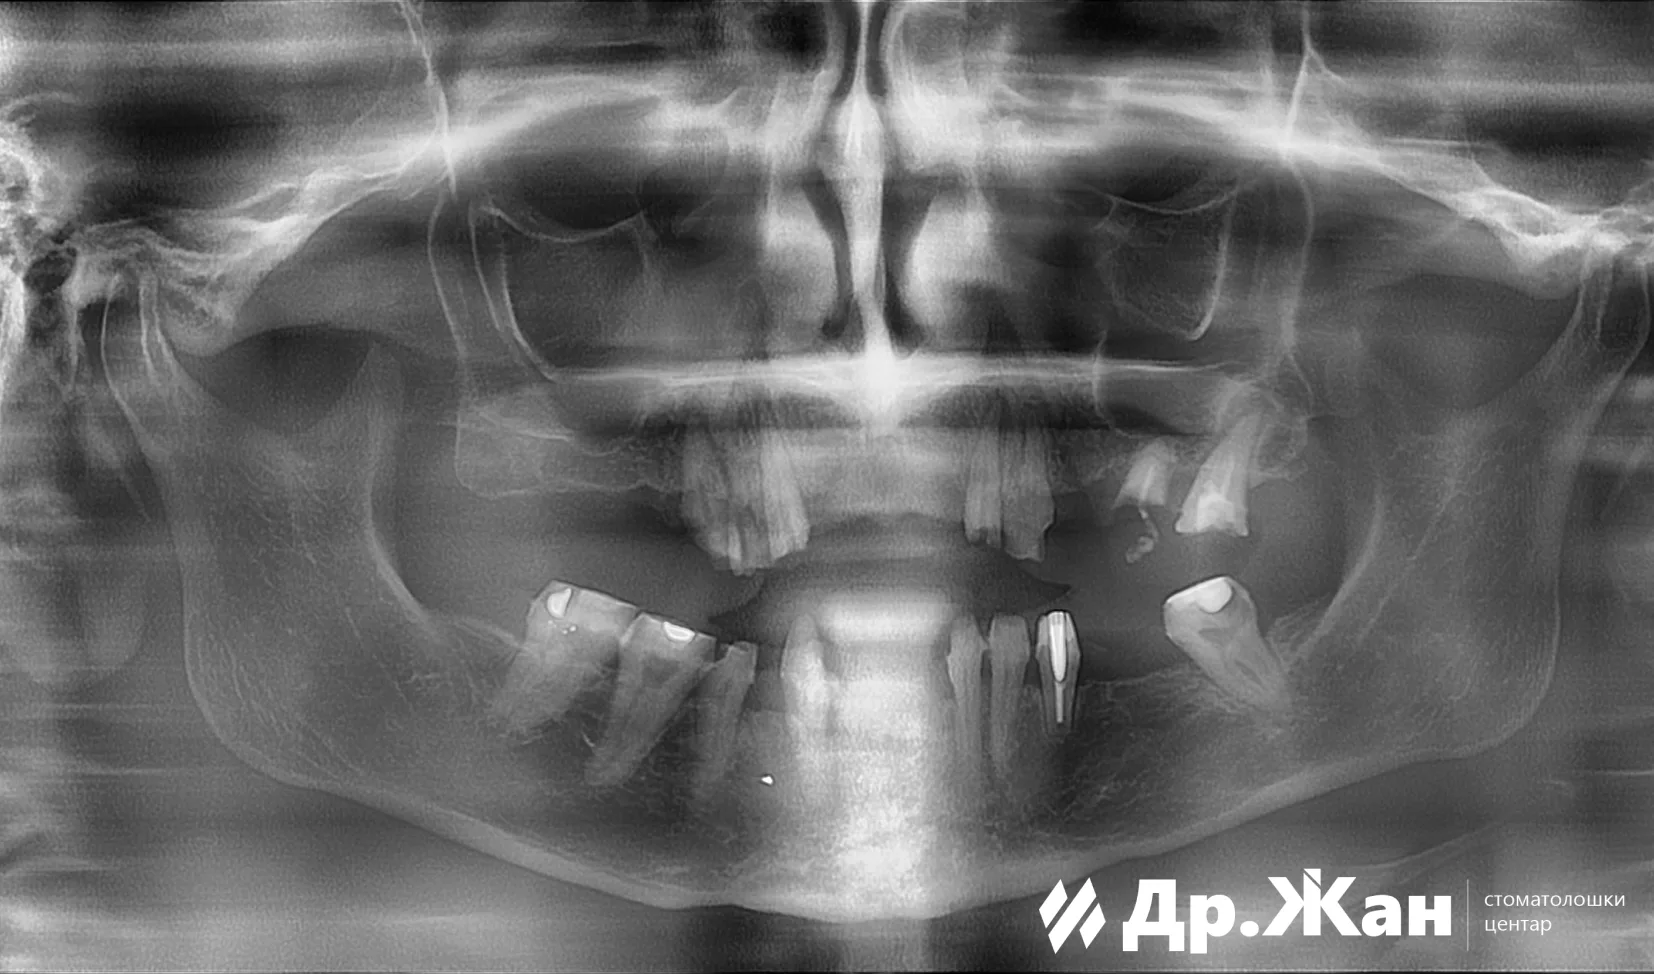

Пародонтитис и длабок кариес

По внимателно испитување и анализа, планот беше да се извлечат сите заби во горната вилица, а некои да се задржат во долната вилица за полесен премин за пациентката. Веднаш по вадењето, беа поставени 6 импланти во горната вилица и 5 забни импланти во долната вилица. Имплантската терапија беше извршена со дигитален работен тек и со употреба на хируршки водичи. ѝ беа обезбедени фиксни привремени заби за периодот на заздравување.

ПРЕД